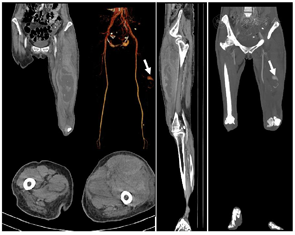

甲泼尼龙500mg×3天,继以逐渐减量(250mg×3天、160mg×3天、80mg×5天);环孢素75mg,bid;环磷酰胺0.8g qw×3次,余予以全覆盖抗感染以及吡非尼酮600mg tid /d抗纤维化治疗。患者于11月21日诉左侧大腿肿痛。血常规:血红蛋白:65g/L;血小板:89×109/L。凝血功能PT14.4秒、APTT42.1秒、纤维蛋白原1.24g/L。不能排除下肢肌间出血可能,急行床边B超:左大腿软组织区包块--血肿?行下肢动脉CT:考虑左侧大腿肌间血肿形成(图5)。介入科会诊后行超选择性左侧股深动脉-穿动脉栓塞术(图6)。患者出血停止,血肿吸收,好转出院。目前仍在随访中。